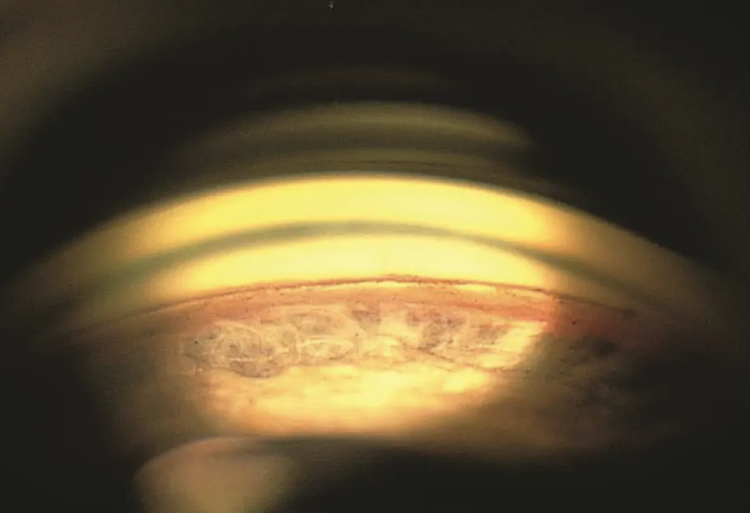

Primary angle-closure suspect (PACS) is defined as non-visibility of the trabecular meshwork for 180° or more in the absence of PAS with normal intraocular pressure (IOP). Primary angle closure (PAC) can be further classified as appositional or synechial.

On the other hand, primary (synechial) angle closure (PAC) refers to an eye in which portions of the anterior chamber angle are closed permanently by PAS with more than 180° of iridotrabecular contact with or without raised IOP.